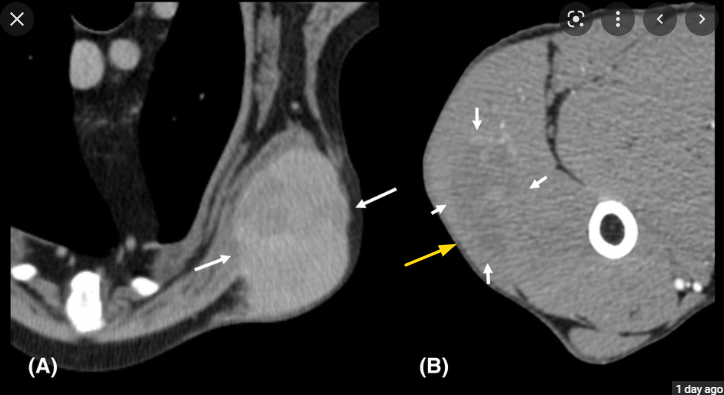

반려견 비만 세포종 수술에서 CT의 역할

결론적으로 말하자면 수술의 범위를 평가하기 위한 용도로는 부적절하고

전이 양상을 평가하기 위한 전통적 목적에서 CT 가 사용되어야 한다고 한다.

노란색 화살표에 종양의 존재는 확인되지만 경계가 명확하지 않은것이 그 이유라고 할 수 있다.